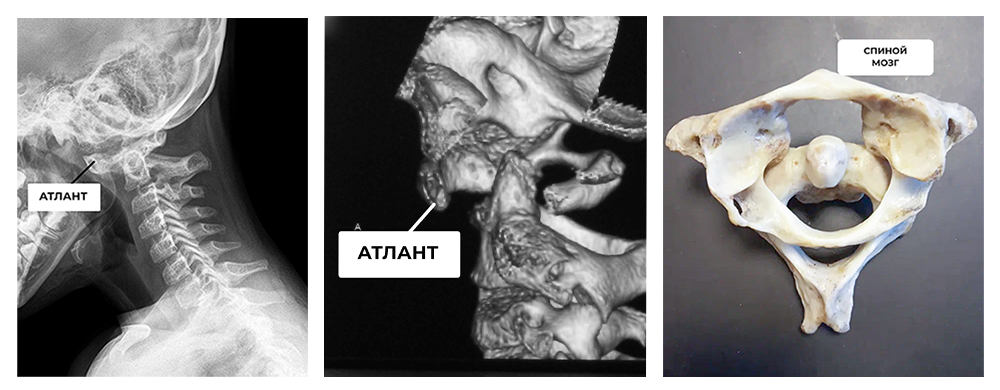

Наиболее опасной областью нестабильности является сочленение первого (атланта) и второго (аксиса) позвонков. Это сложная по строению и очень нагружаемая по функции область. Атланто-аксиальное сочленение обеспечивает 50% поворота в шее, сохраняя спинной мозг и кровоток в позвоночных артериях, питающих головной мозг. К сожалению, в этой области наиболее часто возникают пороки развития и нарушения формирования. Они могут встречаться как у внешне здоровых детей, так и сопровождаться разной степенью кривошеи и неврологическими расстройствами, вплоть до тетраплегии (паралича конечностей) и нарушения дыхания.

На фото: атланто-аксиальная нестабильность у ребенка 9 лет. Атлант смещен вперед, а спинной мозг оказывается сдавлен между дугой атланта и зубовидным отростком.